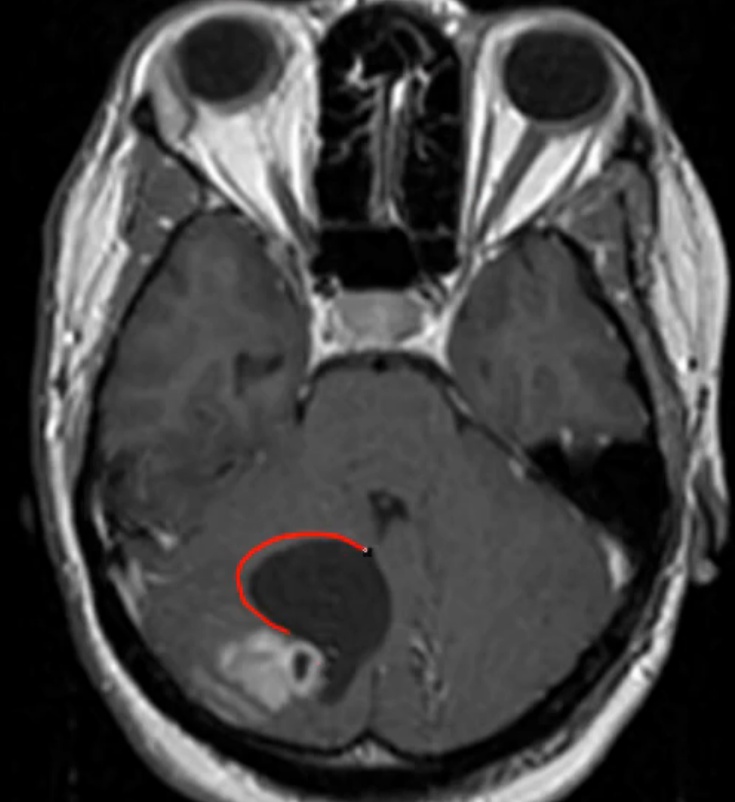

Cavernous Hemangioma

Cavernous hemangiomas are vascular malformations that frequently involve the deeper tissues of the body, such as the liver and brain. Gross examination of hemangiomas reveals a "mulberry-like" appearance due to their purple vascular clusters. Histologically, they are composed of abnormal, dilated blood vessels with a thin adventitia lacking elastic fibers and smooth muscle. The reduced structural support gives them a tendency to leak, causing recurrent hemorrhage.

Most patients with cavernous hemangiomas are asymptomatic, although hemangiomas in the brain may cause neurologic deficits and seizures due to compression of the surrounding tissue and irritation from recurrent bleeding. Surgical resection is indicated for lesions causing intractable epilepsy or progressive neurologic deficits.